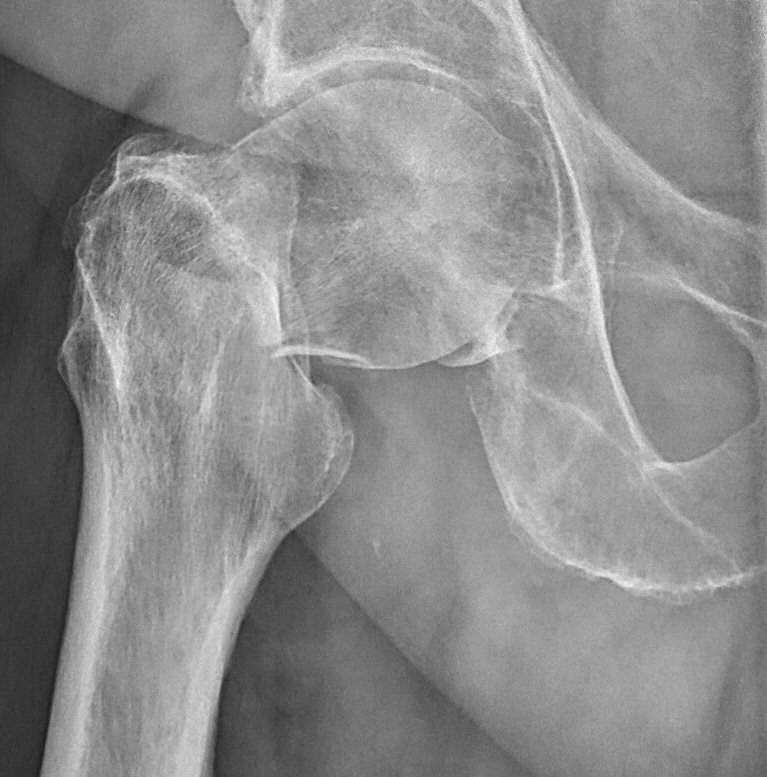

- Cervikal, fraktur av kollum femoris. Klassificeras enligt Garden som bedöms på frontalbild. Det finns något olika tolkningar av denna klassifikation. Ofta används istället "Garden 1-2" för odislocerad eller måttligt dislocerad fraktur och "Garden 3-4" för mer dislocerad.

- Garden 3: genomgående fraktur med kontakt inferiort, varusställd [1]